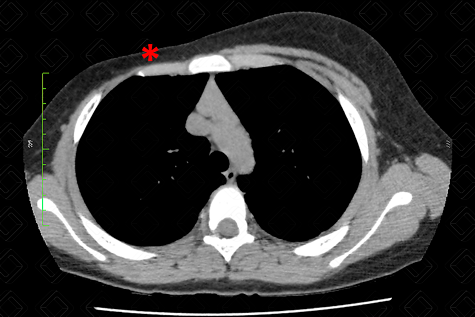

Texto alternativo para a imagem Figura 2. Créditos: Dra. Elazir Mota - Rio de Janeiro/RJ

Descrição da figura 2: Tomografia computadorizada do tórax evidenciando assimetria torácica importante, por ausência dos músculos peitorais maior e menor direitos (asterisco vermelho).

• Ressonância magnética/tomografia computadorizada: Em geral, não são exames necessários para este diagnóstico. Em ambos, fica nítida a evidente assimetria torácica e a ausência de um ou ambos os músculos peitorais (figura 2).